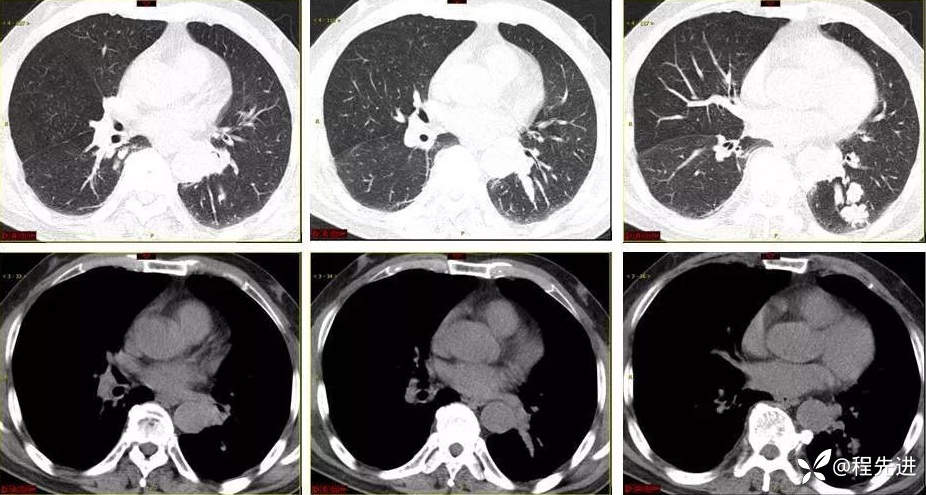

9月特别精彩病例|咳嗽伴咯血4月余,重点讨论胸部|结果已公布

患者性别:男

患者年龄:65岁

主诉:咳嗽伴咯血4月余

现病史:患者4月余前劳动后出现咳嗽,为阵发性干咳,以中午为主,后出现咯血,呈鲜红色,共5-6次,量最多时约50ml,约有3-4次。外院予以对症治疗(具体不详)后好转,1周前患者又出现咯血一次,约10ml。患者病程中无发热,时有胸闷,无胸痛,无呼吸困难,无盗汗,无恶心呕吐,无呕血黑便,食欲睡眠可,二便正常,体重无明显下降